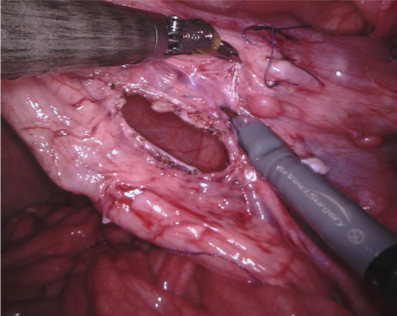

In 2017 we organized a follow-up challenge222https://endovissub2017-roboticinstrumentsegmentation.grand-challenge.org where a team at Intuitive Surgical manually segmented images from porcine robot assisted nephrectomy procedures. We aimed to improve on the previous challenge by first increasing the label quality by using hand-created labels rather than automatic labelling, secondly by adding greater variance in the background by using 10 separate procedures and finally by providing more type and part labels for the instruments.

We provided the first 225 frames of 8 sequences as training data and kept the last 75 frames of those 8 sequences as test data. 2 of the full 300 frame sequences were kept as test sequences. Test labels were kept hidden from the participants. Our datasets contain 7 different robotic surgical instruments. The Large Needle Driver, Prograsp Forceps, Monopolar Curved Scissors, Cadiere Forceps, Bipolar Forceps, Vessel Sealer and additionally a drop-in ultrasound probe, which is typically held in the jaws of the Prograsp Forceps instrument. Samples from the training datasets are depicted in Fig. 2 and examples of the different instrument types are shown in Figure 3 and 4.